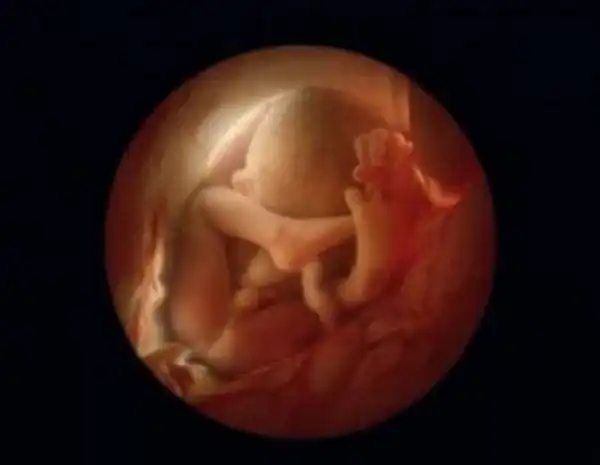

18 недель. Около 14 см. Зародыш теперь может воспринимать звуки из внешнего мира.

19 недель..